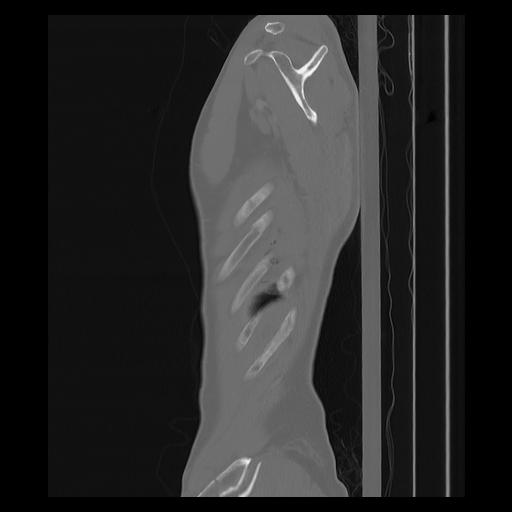

33 PULMON,CE,Sagittal,3.000,PULMON,Sagittal,